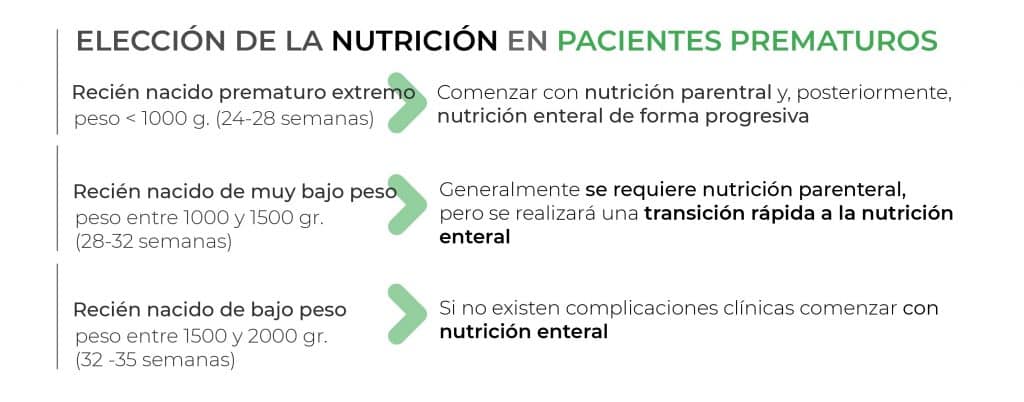

Está indicada cuando el paciente necesita un soporte nutricional individualizado al no existir o no ser suficiente la alimentación oral para cubrir sus necesidades energético-proteicas. Las principales situaciones clínicas en las que se dan estas características son (4,7):

La nutrición parenteral consiste en la administración de nutrientes a través del empleo de un acceso venoso con la finalidad de cubrir las necesidades metabólicas del paciente. Este soporte se empleará en niños que presenten signos o riesgo de desnutrición cuando la vía oral o enteral no se encuentren disponible y se mantendrá hasta que el paciente logre tolerar la alimentación por el método enteral.

- En pacientes muy prematuros (< 30 semanas de gestación) o con un peso inferior a 1000 gr.